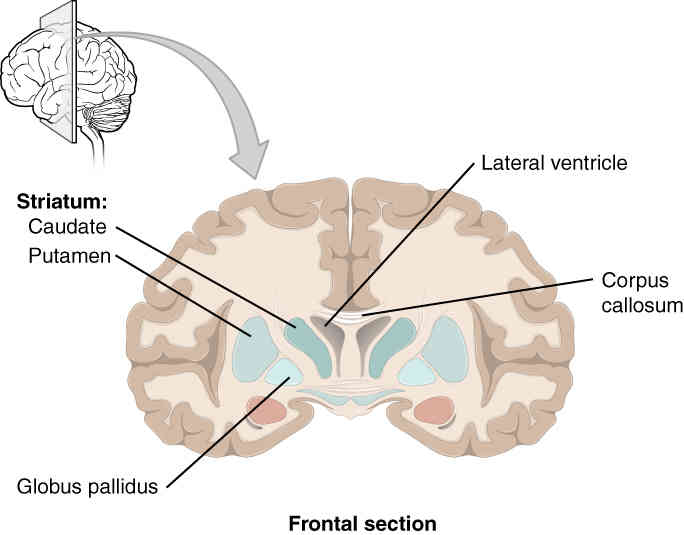

This page is under construction. For now, it is just a resource of the images found in the OpenStax Anatomy and Physiology Handbook. It wil slowly change into a revision tool. Each slide has a number. Use this to refer to the slide. When completed, it will have an unlabelled section, with labelled slides in parallel. On the unlabelled slides, write your answer and use the labelled slide to assess yourself. Keep track by also noting the number on each slide. Improvement at each attempt is important, more so than full marks on a first attempt.